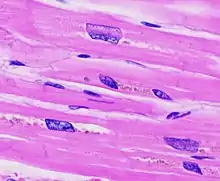

The ventricles are the chambers in the heart responsible for pumping blood either to the lungs (right ventricle) or to the rest of the body (left ventricle). Ventricular hypertrophy may be divided into two categories: concentric hypertrophy and eccentric hypertrophy. These adaptations are related to how the cardiomyocyte contractile units, called sarcomeres, respond to stressors such as exercise or pathology. Concentric hypertrophy is a result of pressure overload on the heart, resulting in parallel sarcomerogenesis (addition of sarcomere units). Eccentric hypertrophy is related to volume overload and leads to the addition of sarcomeres in series.[3]

Concentric hypertrophy is characterized by an addition of sarcomeres (the contractile units of cardiac cells) in parallel. The result is an increase in thickness of the myocardium without a corresponding increase in ventricular size. This is maladaptive largely because there is not a corresponding proliferation of the vasculature supplying the myocardium, resulting in ischemic areas of the heart. Ultimately, this response can be compensatory for a duration, and allow for improved cardiac function in the face of stressors. However, this type of hypertrophy can result in a dilated ventricle which is unable to effectively pump blood, leading to heart failure.[4] When stressors that encourage this concentric hypertrophy are reduced or eliminated (either surgically corrected in the case of cardiac defects, or hypertension is reduced from diet and exercise) it is possible for the heart to undergo 'reverse remodeling', returning to a somewhat more 'normal' state instead of progressing to a dilated, pathologic phenotype.

Eccentric hypertrophy is generally regarded as healthy, or physiologic hypertrophy and is often termed "athlete's heart." It is the normal response to healthy exercise or pregnancy,[5] which results in an increase in the heart's muscle mass and pumping ability. It is a response to 'volume-overload', either as a result of increased blood return to the heart during exercise, or a response to an actual increase in absolute blood volume as in pregnancy. This increase in pumping ability is the result of the addition of sarcomeres in series, which enables the heart to contract with greater force.[6] This is explained by the Frank Starling mechanism, which describes the sarcomere's ability to contract with greater force as more of the elements of its contractile units become engaged. This response can be dramatic; in trained athletes have hearts that have left ventricular mass up to 60% greater than untrained subjects. Rowers, cyclists, and cross-country skiers tend to have the largest hearts, with an average left ventricular wall thickness of 1.3 centimeters, compared to 1.1 centimeters in average adults. Though eccentric hypertrophy is termed 'athlete's heart' it is typically only found in individuals who are aerobically conditioned. For example, weight lifters tend to undergo remodeling which more closely resembles concentric hypertrophy, as the heart does not experience a volume-overload, but instead responds to transient pressure overload as a consequence of increased vascular resistance from pressures exerted on arteries by sustained muscular contraction.